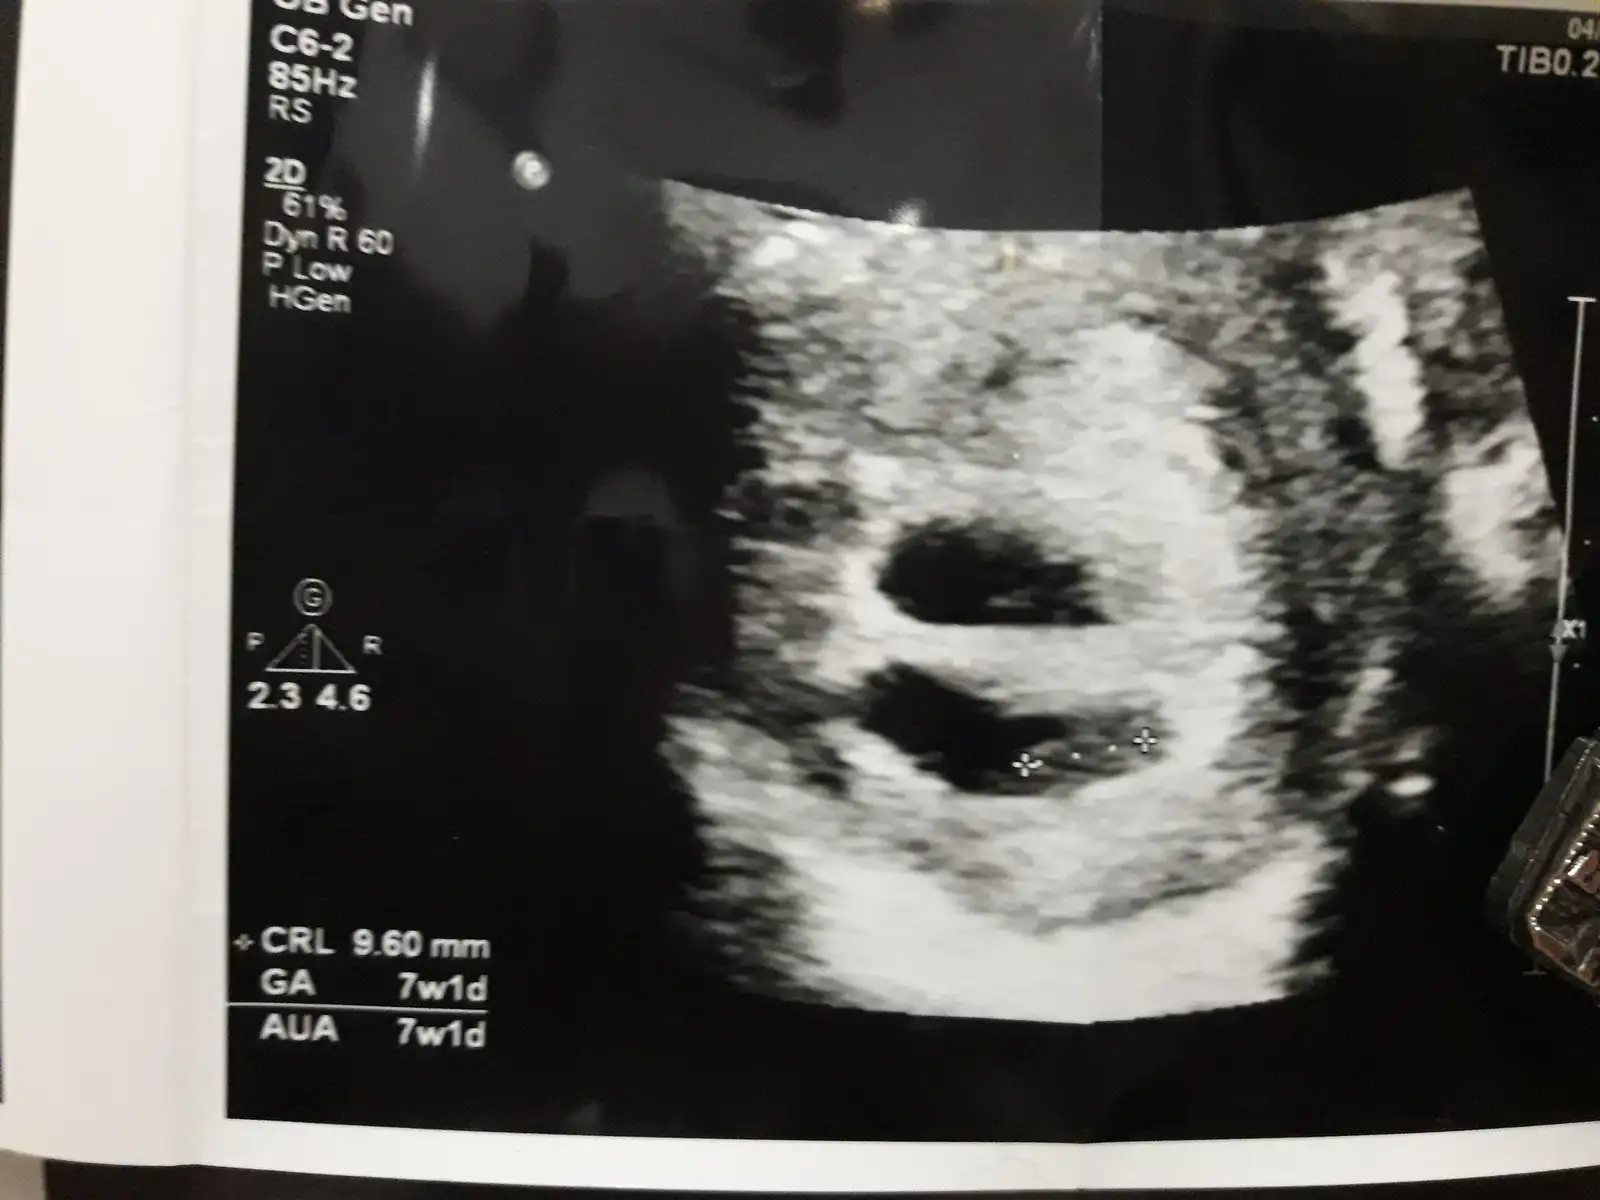

Oyy maşallah yaaa, ne sevimliler. Kucagına aldığın zamanları da görün inşallah. Çok tatlılar 7+1gösterıyorla. Yani 8. Haftanın içindesinEki Görüntüle 2212178 Eki Görüntüle 2212179 teyzeleri bunlar minnaklar. Video cek dedim esime bizeye benzediklerinde cekeriz dedi tamda doktor geldi uzatamadim mevzuyu.![]()

Bende onu sorucaktim doktora nasillar dedim fistik gibiler dedi guldu. Biri 7+1 biri 6+6 gosteriyo. Normalde bakinca 6+4uz bugun. Yemisler beni simdidenOyy maşallah yaaa, ne sevimliler. Kucagına aldığın zamanları da görün inşallah. Çok tatlılar 7+1gösterıyorla. Yani 8. Haftanın içindesin![]()

Maşallah canım, gelişimleri iyi demek ki :)Bende onu sorucaktim doktora nasillar dedim fistik gibiler dedi guldu. Biri 7+1 biri 6+6 gosteriyo. Normalde bakinca 6+4uz bugun. Yemisler beni simdidenbiri 2 gun biri 4 gun onde masallahhhh kuzulara